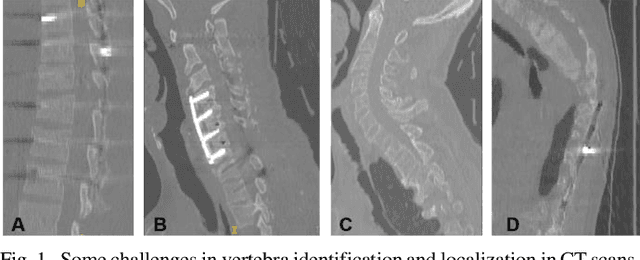

Abstract:Accurate identification and localization of the vertebrae in CT scans is a critical and standard preprocessing step for clinical spinal diagnosis and treatment. Existing methods are mainly based on the integration of multiple neural networks, and most of them use the Gaussian heat map to locate the vertebrae's centroid. However, the process of obtaining the vertebrae's centroid coordinates using heat maps is non-differentiable, so it is impossible to train the network to label the vertebrae directly. Therefore, for end-to-end differential training of vertebra coordinates on CT scans, a robust and accurate automatic vertebral labeling algorithm is proposed in this study. Firstly, a novel residual-based multi-label classification and localization network is developed, which can capture multi-scale features, but also utilize the residual module and skip connection to fuse the multi-level features. Secondly, to solve the problem that the process of finding coordinates is non-differentiable and the spatial structure is not destructible, integral regression module is used in the localization network. It combines the advantages of heat map representation and direct regression coordinates to achieve end-to-end training, and can be compatible with any key point detection methods of medical image based on heat map. Finally, multi-label classification of vertebrae is carried out, which use bidirectional long short term memory (Bi-LSTM) to enhance the learning of long contextual information to improve the classification performance. The proposed method is evaluated on a challenging dataset and the results are significantly better than the state-of-the-art methods (mean localization error <3mm).